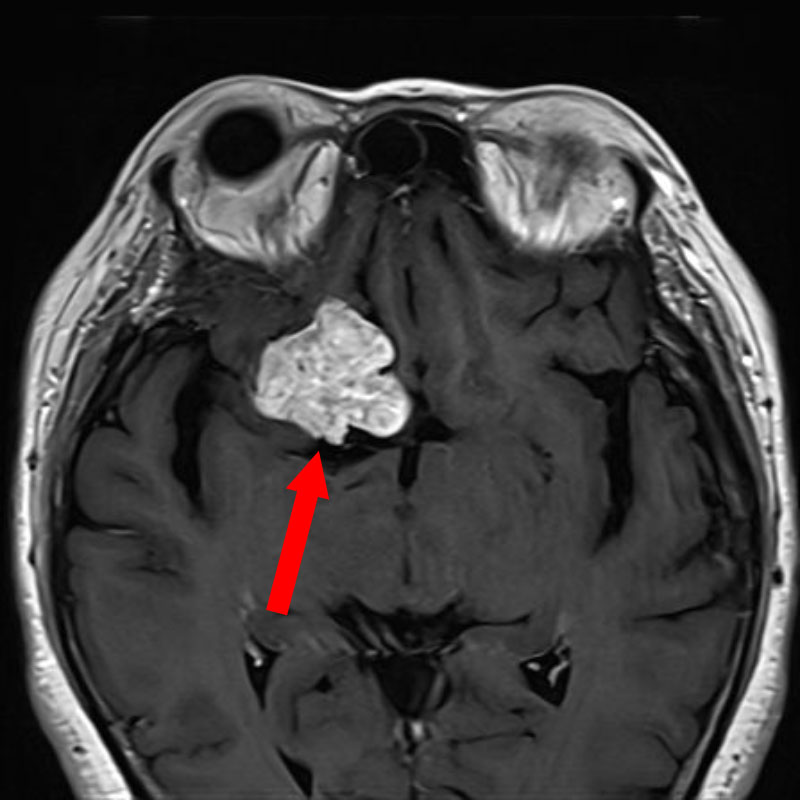

手術前1

手術前2